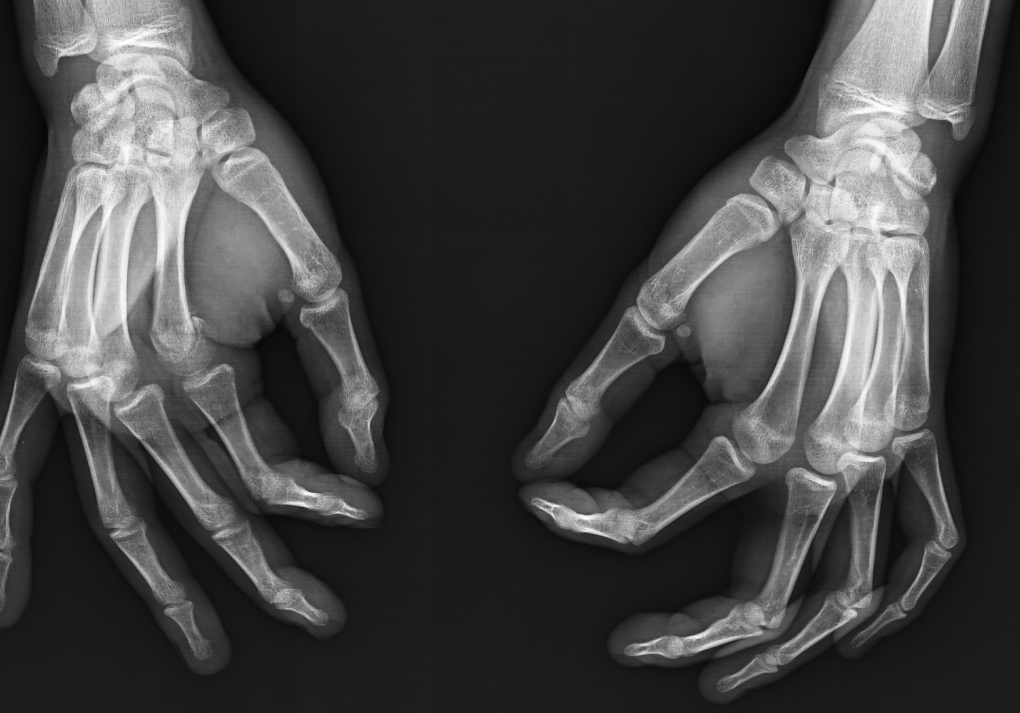

To continue with this method & estimate your own bone age, you’ll need an xray of your non dominant hand, including your wrist. We’re going to be evaluating a total of 13 bones.

I’ve worked my ass off to create the following reference sheets, so here’s what you’re going to do with them.

I added references for stages A (Completely unfused), E-F (Partial fusion, basically late stages of puberty), and I (Complete Fusion)

You will have to eyeball this now using your own xrays, I’ve given three examples and some wiggle-room for letters using a reference bar (green-red) below the image, write down your estimated guesses in a text file until you finish all 13 bones.

Don’t doubt yourself, eyeballing isn’t perfect but it still works well, just choose & continue.